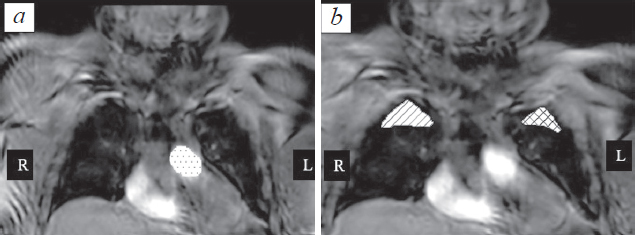

Fig. 2. Coronal reconstructions of image with dynamic contrast enhancement. а – The choice of ROI for AIF. When selecting this area of interest, MPR reconstructions should be used to exclude pulmonary arteries from the area of interest; b – selection of areas of interest in the coronal plane for comparison with the published data

Рис. 2. Корональные реконструкции серий изображений с динамическим контрастным усилением. а — Выбор ROI для определения функции AIF. При выборе данной области интереса следует использовать MPR-реконструкции для исключения из зоны интереса легочных артерий; b — выбор областей интереса в корональной плоскости для сравнения с приведенными в литературе данными

In addition to the selection of the zone of interest described above, ROIs oriented in the coronal plane were considered. Such a choice of the area of interest reflects to a lesser extent the physiological characteristics of the blood supply to the lungs; therefore, this projection was used only to calculate the arterial input function (AIF).